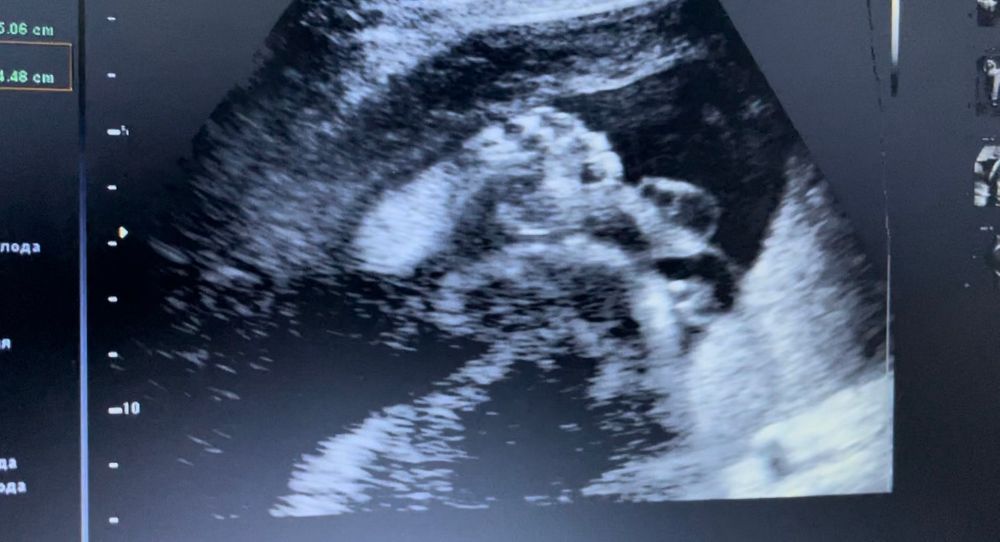

Была на УЗИ платно в 28.4, и в стационаре на сроке 29.4.

Вес 1650гр, рост сказали только на платном УЗИ, был 38см. Сказали, что с сыном все прекрасно, длинные ноги и большая ступня)

В 3Д посмотреть на личико не дал ((